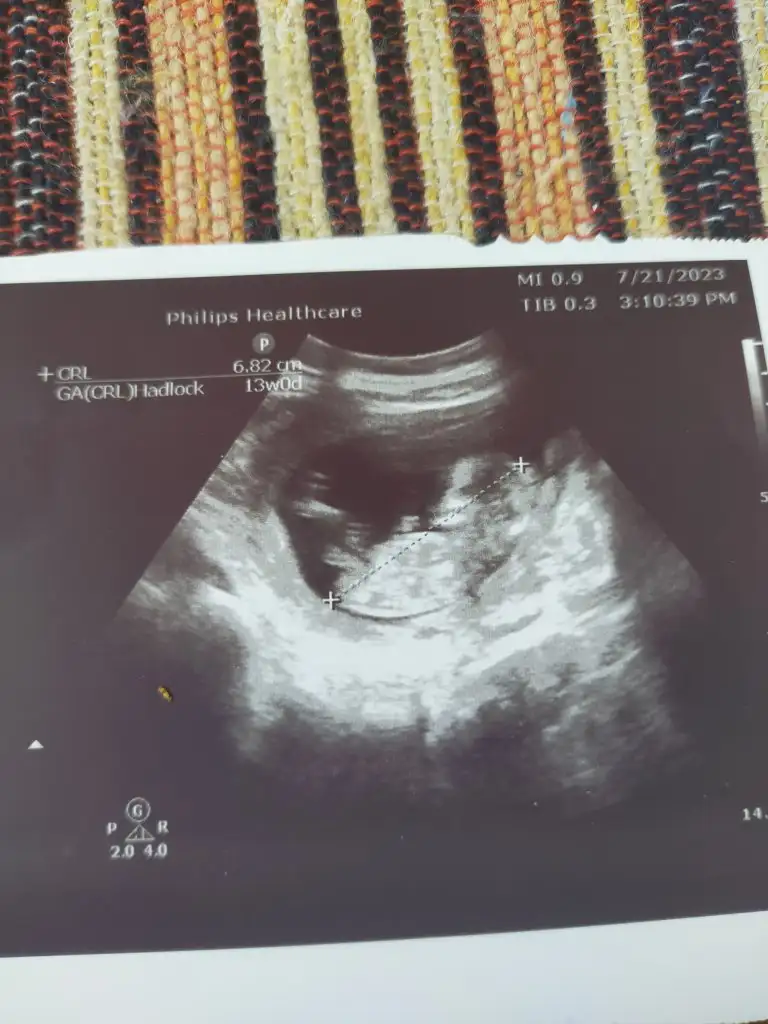

ManyakPrenses ManyakPrenses Merhabalar bende bir tahmin alabilirmym hem 8 hem 11. Hafta ektedir. Teşekkürler

Merhabalar, 8+3 haftalık ve karından ultrason. Sizce cinsiyeti ne olabilir acaba?😬